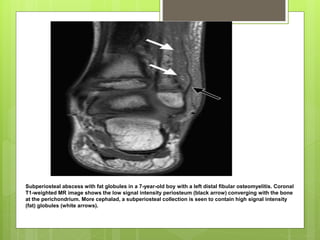

Subperiosteal abscess with fat globules in a 7-year-old boy with a left distal fibular osteomyelitis. Coronal

T1-weighted MR image shows the low signal intensity periosteum (black arrow) converging with the bone

at the perichondrium. More cephalad, a subperiosteal collection is seen to contain high signal intensity

(fat) globules (white arrows).

 MAGNETIC RESONANCEIMAGING (MRI) • helpful in cases of doubtful diagnosis, and particularly in suspected infection of the axial skeleton.  It is also the best for bone marrow inflammation.  It is extremely sensitive, even in the early phase of bone infection, and it can therefore assist in differentiating between soft-tissue infection and osteomyelitis..

Subperiosteal abscess withfat globules in a 7-year-old boy with a left distal fibular osteomyelitis. Coronal T1-weighted MR image shows the low signal intensity periosteum (black arrow) converging with the bone at the perichondrium. More cephalad, a subperiosteal collection is seen to contain high signal intensity (fat) globules (white arrows).